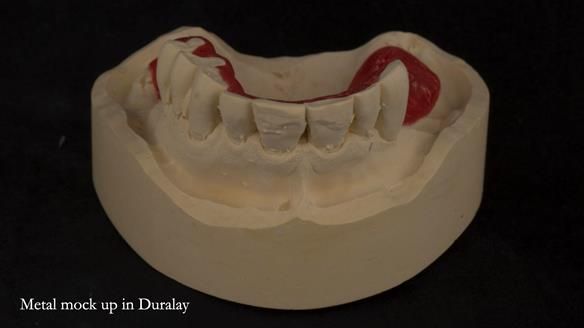

We began with the lower jaw.

A posterior implant 47 had lost integration and was infected. This was removed.

Ken did not want further implant surgery.

Instead, we made a Scandinavian-style, metal-based lower RPD.

It was made promptly, then relined gradually over the following year

to optimise fit, comfort, and support.

It’s worth saying that the lower denture in this case was made in the early days of Rowan and me using the Scandinavian approach. Rowan cast the metalwork himself for this denture.

Looking back, we would make this denture more hygienic now. The design and finish would be more refined and delicate, particularly when compared with the upper metalwork, which was made later using Chris Hesketh’s chrome work. I will discuss this in detail at the study club.

That said, the lower denture worked beautifully. It did exactly what it was meant to do, even though, by today’s standards, it looks a little agricultural.